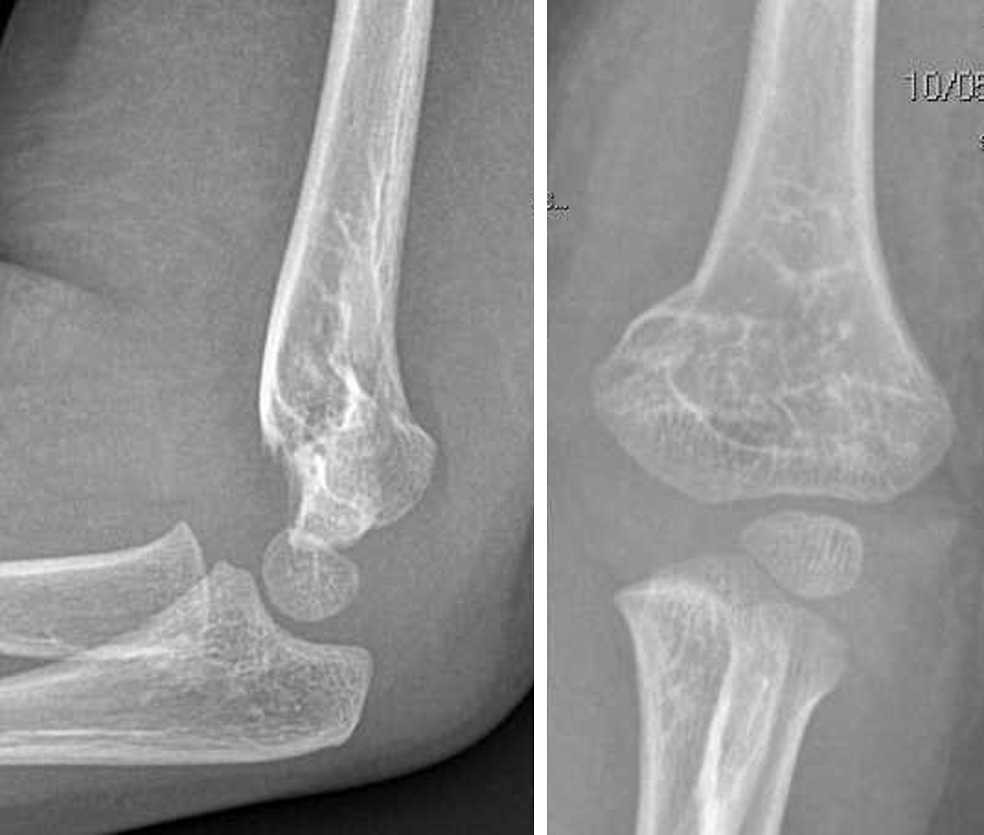

Frattura Sovracondiloidea Omero. Pseudoartrosi serrata Persistenza della rima di frattura. Nella maggior parte di. Radiografia in proiezione laterale di frattura sovracondiloidea dellomero Lomero distale si può fratturare sia per traumi diretti per cadute sul gomito che per traumi indiretti come la caduta sul palmo della mano a gomito esteso oppure per torsioni del gomito. Una frattura sopracondilare è una lesione allomero o osso superiore del braccio nel punto più stretto appena sopra il gomito.

Le rigidità post-traumatiche di gomito sono molto frequenti. La frattura è solitamente trasversale o obliqua e al di sopra dei condili e degli epicondili mediali e laterali. Una frattura dellomero sopracondilare è una frattura dellomero distale appena sopra larticolazione del gomito. Risultato definitivo 3 E stata accertata da Moore che tale affezione si instaura su un particolare terreno spasmofilo. Pseudoartrosi serrata Persistenza della rima di frattura. Essi sono spesso causati da una caduta su un gomito tesa o di un colpo diretto al gomito.

La regione sovracondiloidea è una sede particolarmente debole nellomero in via di sviluppo. Le fratture sovracondiloidee dellomero rappresentano la più comune lesione scheletrica della regione del gomito in traumatologia pediatrica con un picco massimo di in-cidenza tra i 5 ed i 7 anni ed una prevalenza nel sesso maschile e nel lato sx rapporto MF. FRATTURA DELLOSSO La frattura è il risultato di un sovraccarico singolo o multiplo dellosso che si verifica nella frazione di un millisecondo. La frattura dellomero provoca un dolore. Fratture e distacchi del massiccio condiloideo dellomero distale - Frattura sovracondiloidea. In tale sede quindi il diametro AP dellome-ro è limitato e ciò determina un punto di debolezza.

Fratture sovracondiloidee sono il più comune tipo di infortunio al braccio superiore nei bambini. La frattura è solitamente trasversale o obliqua e al di sopra dei condili e degli epicondili mediali e laterali. Essi sono spesso causati da una caduta su un gomito tesa o di un colpo diretto al gomito. In tale sede quindi il diametro AP dellome-ro è limitato e ciò determina un punto di debolezza. La frattura sovracondiloidea dellʼomero è la lesione più frequente del gomito nel bambino.

Frattura sovracondiloidea scomposta dell omero dx. Il lato sinistro risulta essere il più colpito. Frattura sovracondiloidea scomposta dell omero dx. Arteria omerale 3 Frattura sovracondiloidea dellomero. Radiografia in proiezione laterale di frattura sovracondiloidea dellomero Lomero distale si può fratturare sia per traumi diretti per cadute sul gomito che per traumi indiretti come la caduta sul palmo della mano a gomito esteso oppure per torsioni del gomito.

Lesioni vascolo-nervose la frattura sovracondiloidea dellomero può provocare una lesione del nervo mediano che scorre estremamente vicino al tessuto osseo quindi anche una lieve scomposizione può venire a determinare uninterruzione di questo nervo PRECOCI - Sindrome di Volkmann. Lesioni vascolo-nervose la frattura sovracondiloidea dellomero può provocare una lesione del nervo mediano che scorre estremamente vicino al tessuto osseo quindi anche una lieve scomposizione può venire a determinare uninterruzione di questo nervo PRECOCI - Sindrome di Volkmann. Radiografia in proiezione laterale di frattura sovracondiloidea dellomero Lomero distale si può fratturare sia per traumi diretti per cadute sul gomito che per traumi indiretti come la caduta sul palmo della mano a gomito esteso oppure per torsioni del gomito. Con questa tecnica il. In tale sede quindi il diametro AP dellome-ro è limitato e ciò determina un punto di debolezza.